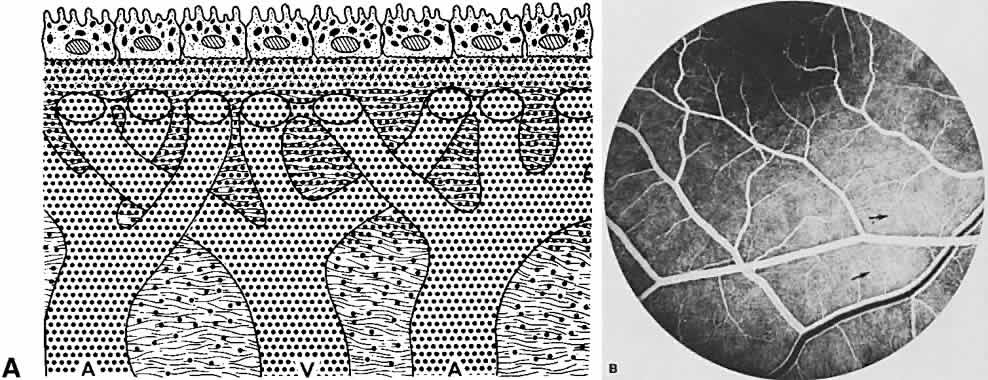

The ocular fundus has two distinctly separate vascular systems—retinal and choroidal—separated by a specialized pigmented monolayer, the retinal pigment epithelium (RPE). Embryologically, the sensory retina and RPE are derived from the inner and outer layers of the optic cup. The choroid and its vasculature lie posterior to the RPE. The fluorescein angiographic patterns of the posterior uvea are, therefore, always partially obscured by the RPE (Fig. 4). The degree of pigmentation and the pathologic changes in this pigmented layer markedly influence the choroidal angiographic appearance. In the interpretation of fundus fluorescein angiograms, the physician must keep in mind and be familiar with the anatomy and interaction of these three layers.

The retina, except for its vasculature, may be regarded as a transparent tissue comprised of tightly packed layers of cells with essentially no extracellular space. The retina is perfused by the central retinal artery and cilioretinal vessels present in 32% of eyes.31 The capillary bed is nonfenestrated and fluorescein does not, therefore, leak from the retinal vessels into the surrounding tissue (Fig. 8). Functionally, the retinal vasculature represents a “closed” system, as opposed to the choroid, in which fluorescein is free to move between the intravascular and extravascular compartments. The retinal circulation normally fills with fluorescein after the choroidal flush; however, a cilioretinal artery fills at the same time as the choroid, preceding the rest of the retinal circulation.

Fluorescein enters the choroidal vascular system via the posterior ciliary arteries. In a very lightly pigmented fundus, these larger choroidal vessels can be seen to fill with fluorescein (Fig. 11). The flow is directed toward the choriocapillaris, the filling of which is called the background choroidal flush (Fig. 12A and B). Normally, this stage begins before the arterial phase of the retinal circulation. If a cilioretinal artery is present, it will fill at the same time (see Fig. 12C). The arm-to-retina circulation time varies, averaging 10 to 20 seconds. The filling of the choriocapillaris occurs in irregular patches, best seen in the posterior pole (see Fig. 12B).41,42

Each patch appears to fill evenly and is the result of separate, irregular areas of choriocapillaris supplied by larger choroidal vessels at slightly different times. The background choroidal flush gradually intensifies and spreads anteriorly toward the ora serrata. The entire choroidal sequence is obscured in the foveomacular area because of the denser pigmentation in the overlying RPE, and possibly the increased amount of xanthophyll in the sensory retina (see Fig. 7).16 To observe the larger choroidal vessels fill with fluorescein, attention must be focused deep to the RPE very early in the study, before the choroidal flush quickly masks these feeding vessels (see Figs. 7, 11B, 12B, 13B, and 14B). As the fluorescein enters the intravascular system of the choroid, it immediately leaks into the extravascular space (see Fig. 12A). This leakage is related to the capillary fenestrations seen in the choriocapillaris. Leakage of fluorescein in the choroid is most intense directly below Bruch's membrane and in the inner choroidal layers (see Fig. 13A). Diffusion then occurs throughout the entire extravascular space to eventually involve the inner scleral fibers (see Fig. 14A). The concentration of fluorescein rapidly equilibrates throughout the inner choroidal layers in both the intravascular and extravascular compartments. The concentration in the extravascular stroma of the outer choroid is probably less. This occurs during the filling phases of the study, usually by the venous phase of the retinal circulation (see Fig. 14). As the study progresses, fluorescein continues to leak from the choroidal vessels. Concurrently, (the density of fluorescein within the vessels becomes less because of the extravascular leakage and dilution by equal distribution throughout the entire blood volume. Therefore, the concentration of fluorescein within the choroidal vessels rapidly becomes less than that in the extravascular choroidal tissue. This occurs in the inner choroidal layers first and can be recognized as the medium-sized choroidal vessels begin to appear as silhouettes against the more concentrated extravascular fluorescence (Fig. 15).